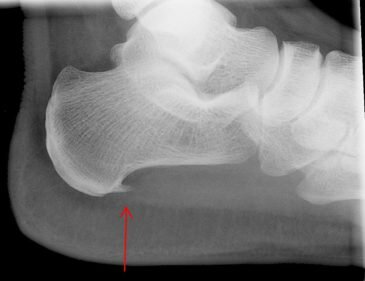

Рентгенографический снимок пяточной шпоры.

Нередко для диагностики пяточной шпоры проводят рентгенологическое исследование. Этот метод диагностики позволяет точно определить причину заболевания и своевременно поставить диагноз. В 40% случаев пяточной боли выявляют наличие шипов в плоскости фасции, в остальных случаях очаг воспаления находится над ней.